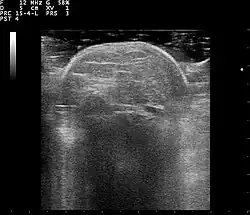

Familial multiple lipomatosis is usually diagnosed through a physical exam via palpation, medical history and imaging studies such as ultrasound, CT scan, or magnetic resonance imaging (MRI). A CT scan is an imaging method that uses x-rays to create images of cross sections of the body, while an MRI uses powerful magnets and radio waves to create images of lipomas and surrounding tissues.[3] Both tests are useful to establish the diagnosis of multiple symmetric lipomatosis, although magnetic resonance imaging provides more details and may be used when lipomas are large, deep, or have infiltrated muscle fibers or nerves. In some cases, a biopsy of the lipomas may be necessary to confirm the diagnosis.[3]